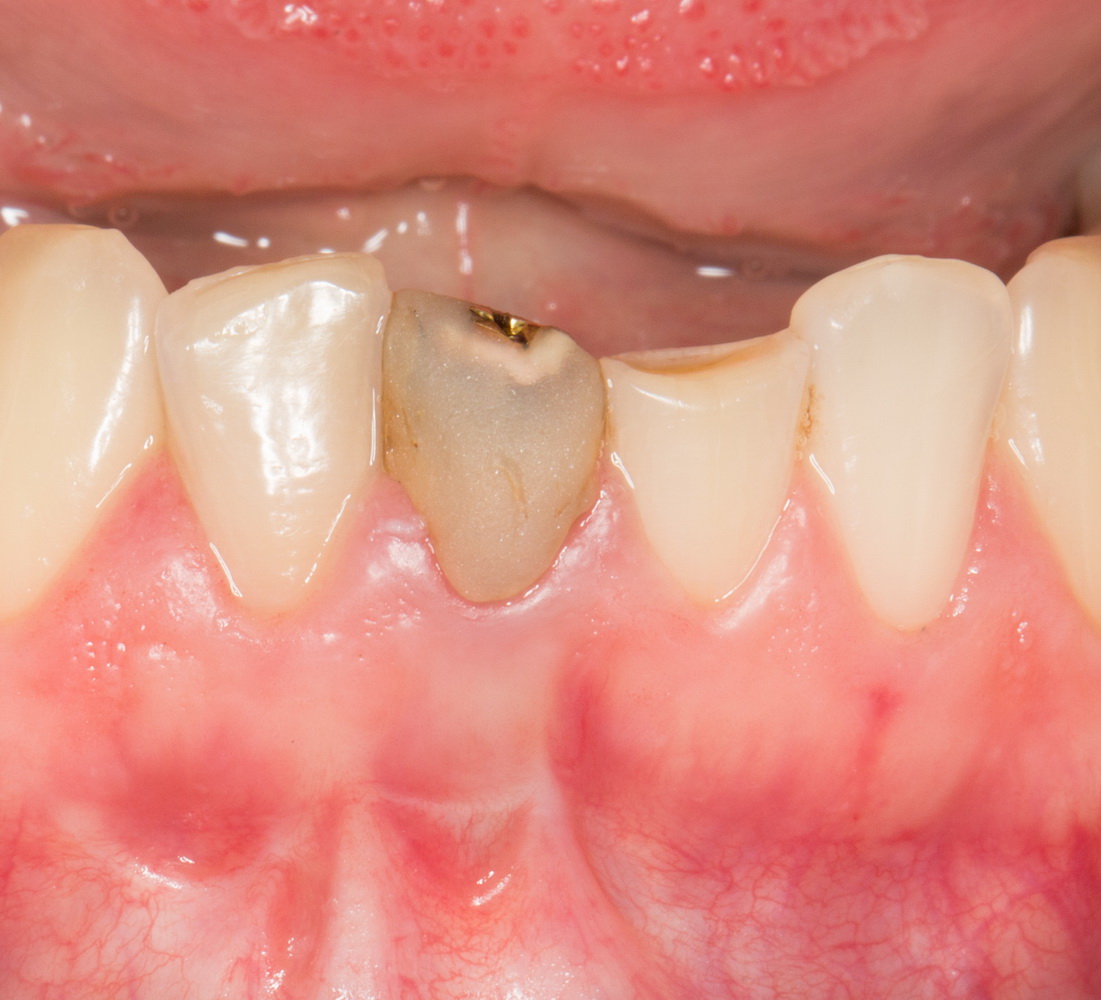

Рекомендации по установке имплантов. Для всех. Часть II.